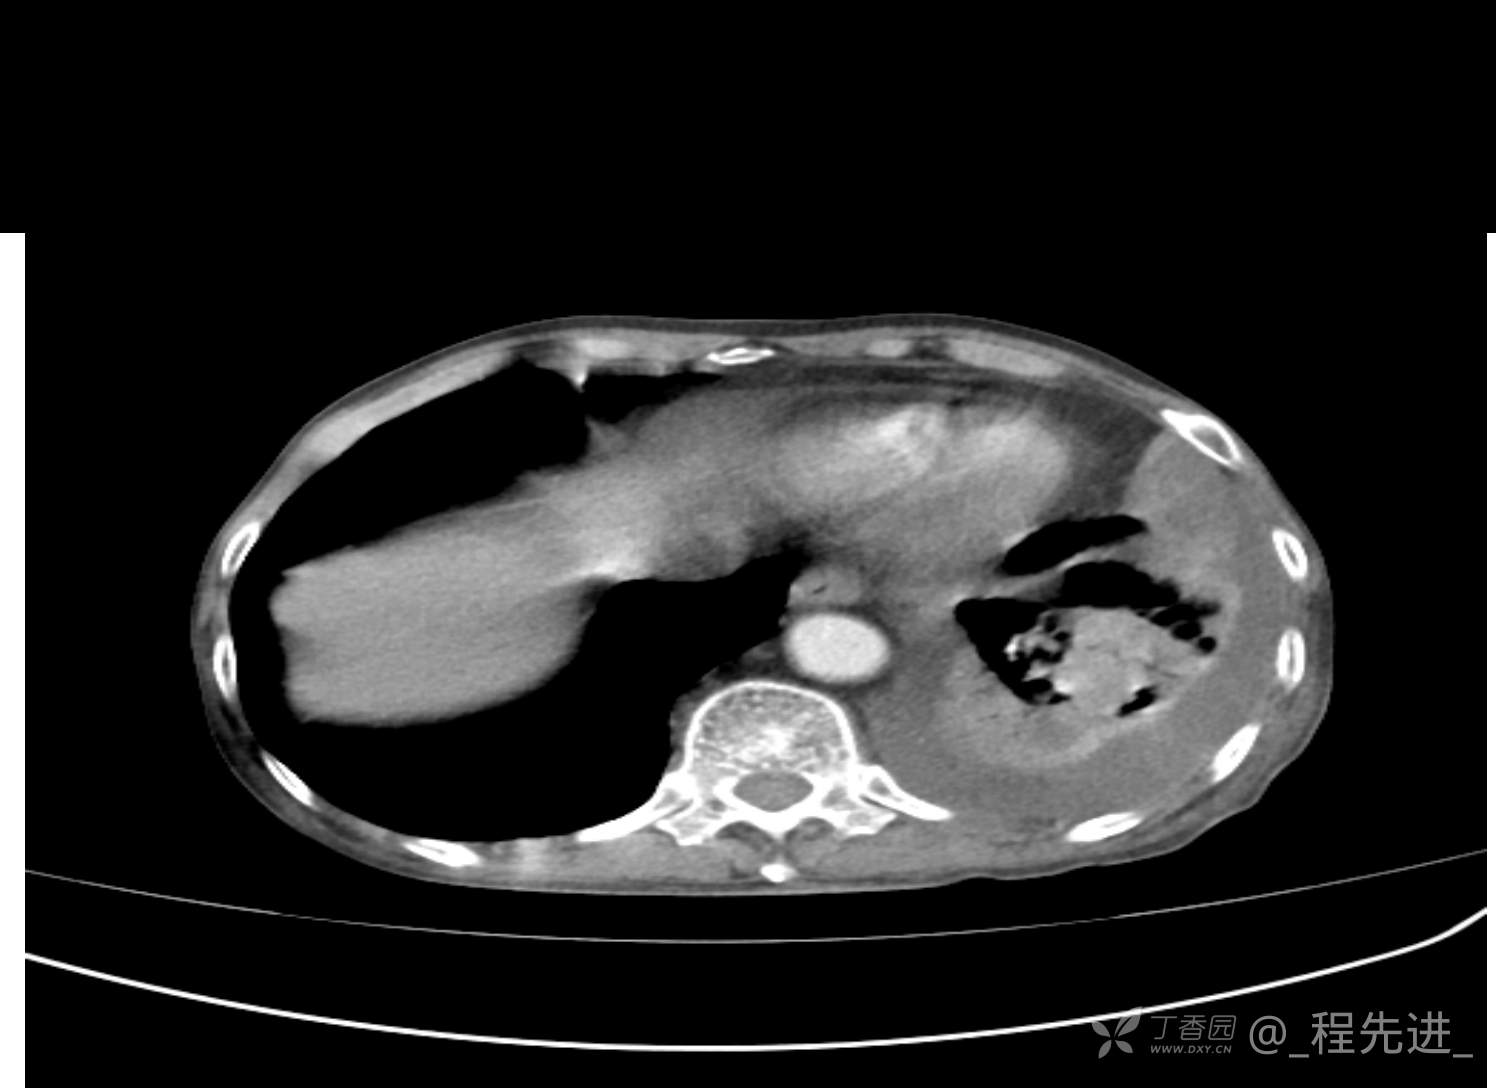

患者性别:男

患者年龄:81岁

简要病史:反复咳嗽、咳痰20余年,加重1周。两肺呼吸音低,可闻及散在干湿啰音。